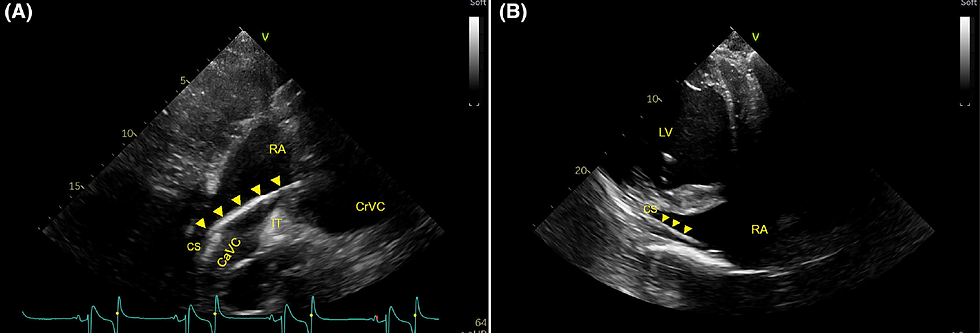

Feasibility of transthoracic echocardiographic guidance for multicatheter electrophysiological mapping studies in horses

🔬The study assessed whether transthoracic echocardiography can reliably guide the real-time placement of multiple electrophysiology catheters in the equine heart—a task that has posed significant challenges in veterinary medicine.